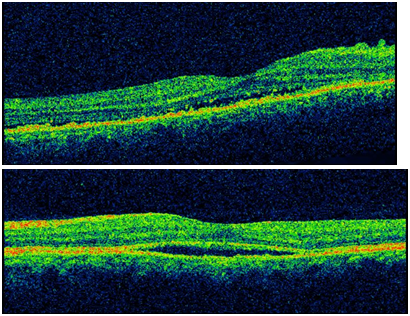

Figure 1B OCT shows neurosensory detachment of the macula.

Central serous chorioretinopathy (CSC) is a chorioretinal disorder characterized by serous detachment of the neurosensory retina. CSC occurs most frequently in mid-life and more often in men than in women. Major symptoms are blurred vision, usually in one eye only and perceived typically by the patient as a dark spot in the centre of the visual field with associated micropsia and metamorphopsia. Normal vision often recurs spontaneously within a few months. The condition can be precipitated by stress and hypercortisolism. Ophthalmoscopic signs of CSC range from mono- or paucifocal RPE lesions with prominent elevation of the neurosensory retina by clear fluid – typical of cases of recent onset – to shallow detachments overlying large patches of irregularly depigmented RPE. The spectrum of lesions includes RPE detachments. Granular or fibrinous material may accumulate in the subretinal cavity. Serous detachment often resolves spontaneously (Figure 1B).

When the retina is detached, the appearance of the outer retinal layer changed; the external limiting membrane persisted, although the IS/OS could not be detected in all eyes, as recently reported by Ojima et al. In the acute phase, the thickness of the probable photoreceptor outer segment increased in the entire area of the detached retina. The increased thickness of the photoreceptor outer segment in the detached retina then gradually decreased, and the outer segment’s appearancechanged to granular until the reattachment.2